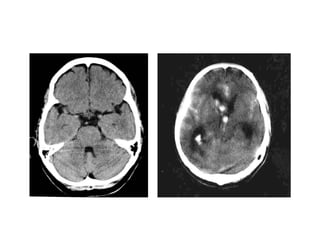

Diffuse brain injury Young CT scan ‘normal’ Very small ‘white dots’ Acceleration – decerelation Shearing force “ Poor GCS with ‘normal’ CT scan” Treatment – based on GCS, ICP & CPP Important to repeat CT after 24-48 hours Edema Delayed hematoma

Diffuse brain injuryYoung CT scan ‘normal’ Very small ‘white dots’ Acceleration – decerelation Shearing force “ Poor GCS with ‘normal’ CT scan” Treatment – based on GCS, ICP & CPP Important to repeat CT after 24-48 hours Edema Delayed hematoma